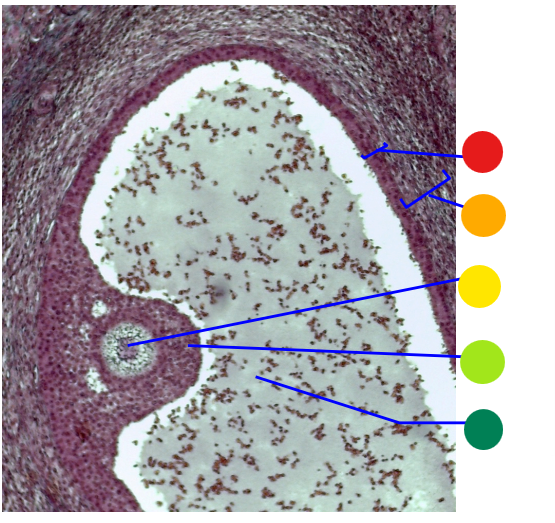

red

primordial follicles

red

primary follicles

red

tunica albuginea

orange

primary oocyte

yellow

primordial follicles

red

granulosa cells

orange

primary oocyte

what is this

primary follicle